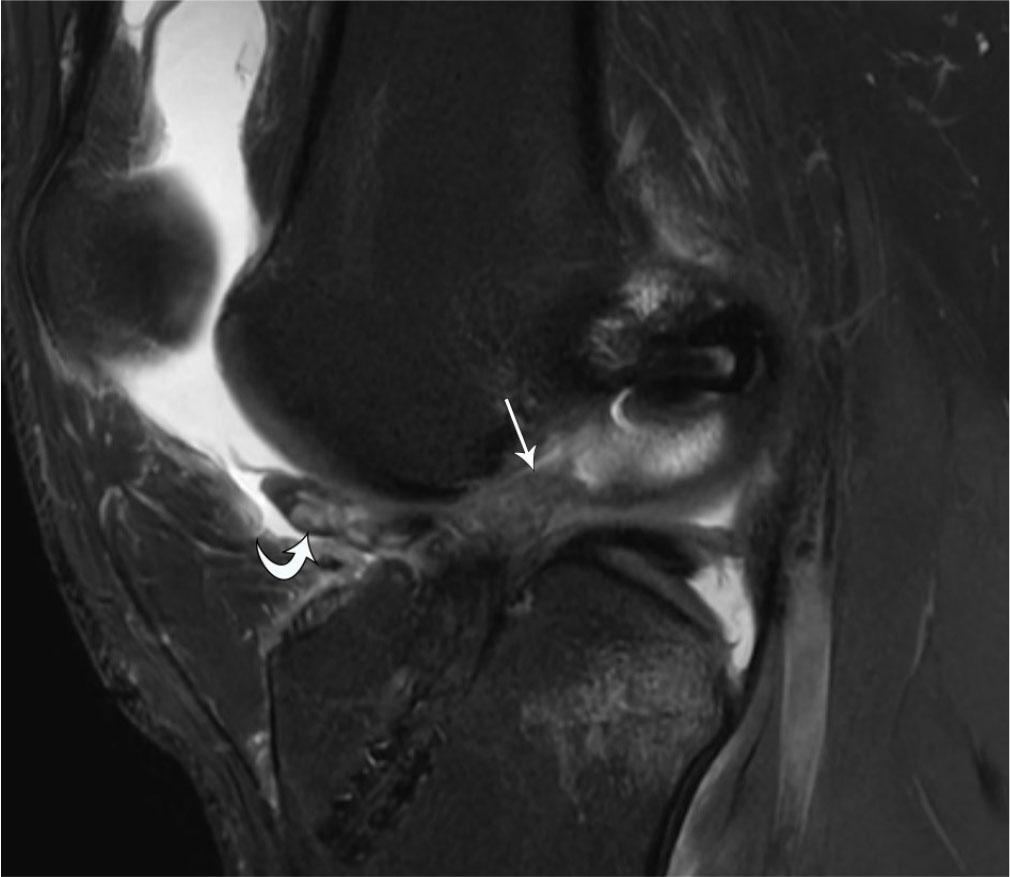

Fig. 4.

39-year-old male with tophaceous gout presenting as a palpable peri-patellar mass. A. Sagittal proton-density-weighted fat-suppressed MR image shows expansile intermediate-signal soft tissue (arrowheads) within the patellar tendon, extending superficial to the anterior patella. B. Axial proton-density-weighted fat-suppressed image shows the mass in the patellar tendon (arrow), as well as additional heterogeneously intermediate-signal nodules within the popliteus tendon (curved arrow) and along the medial femoral condyle (arrowhead), in a distribution characteristic of tophaceous gout